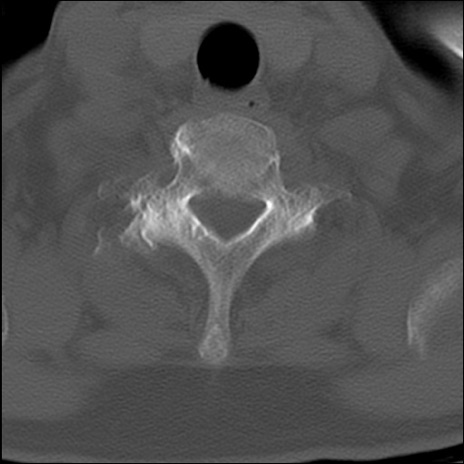

症例48 頚椎CT(横断像)

頚椎CT